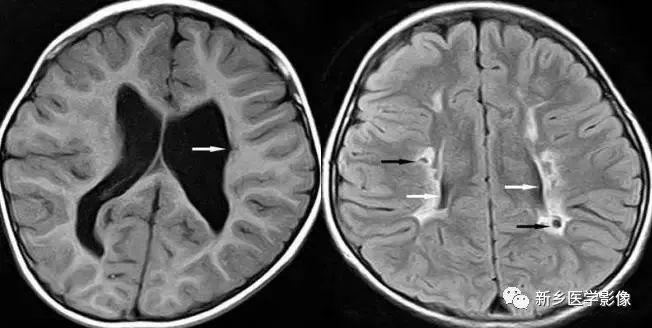

(2)脑裂畸形:胚胎期脑的发育经历6个主要阶段:①背侧诱导阶段;③腹侧诱导阶段;③神经增生阶段;④神经元移行阶段;⑤组织形成阶段;⑥髓鞘形成阶段。脑裂畸形发生在神经元移行阶段。脑裂畸形可累及一侧或双侧大脑半球,脑裂畸形位于侧面.常累及中央前、后回区偶尔位于大脑半球的其他部位。脑裂畸形的裂隙可以很窄,裂隙两侧灰质紧密相贴,称闭合型。裂隙也可以很宽,中间为脑脊液,分离型。

分离型脑裂畸形需要与脑穿通畸形囊肿鉴别.脑裂畸形的裂隙两旁一定为一灰质结构,而脑穿通畸形囊肿周围无脑灰质包绕。裂隙两旁是否为灰质结构是区别脑裂畸形与脑穿通畸形囊肿的可靠征象。裂隙两侧的灰质可不正常,可呈多小脑回样。脑裂畸形也可合并脑灰质异位。

分离型在CT很容易显示.闭合型有时容易漏诊.MRI对裂隙两侧的灰质结构容易辨认。脑裂畸形常合并透明隔缺如.侧脑室扩大,脑裂畸形处脑室边缘不规则.常可见指向裂隙的裂或 三角形憩室存在。

临床上脑裂畸形常表现有癫痫发作,其他神经系统症状可从很轻微到很严重.主要取决于脑裂畸形使脑组织缺损的严重程度。单侧闭合型脑裂畸形症状通常较轻,双侧分离型脑裂畸形症状较明显。